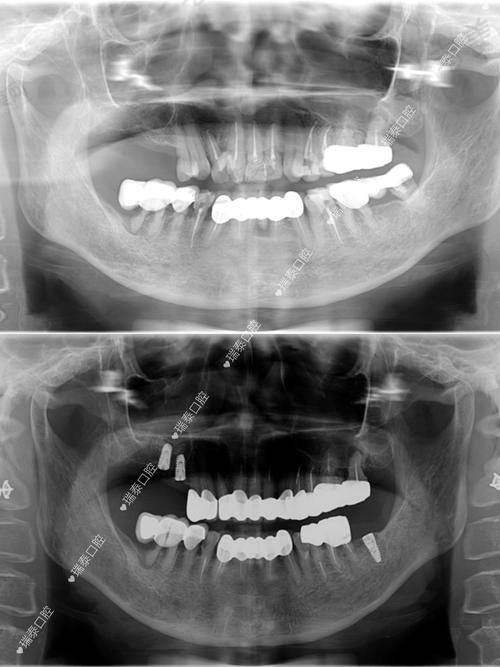

各领域优势:在牙齿种植方面,门诊部拥有精良的技术和经验多的医生,能够为患者提供多种种植方案,确保种植成效的稳定性和美观性。牙齿美白项目采用安心有效的美白技术,能够快速改善牙齿颜色,让患者拥有洁白亮丽的牙齿。牙齿矫正科室运用精良的矫正技术和设备,根据患者的具体情况制定个性化的矫正方案,帮助患者拥有整齐的牙齿。口腔美学修复和口腔综合治疗科室也为患者提供了全方面的口腔诊疗服务。

特色项目优势:武汉左岭博牙口腔门诊部的特色项目众多。牙齿种植项目采用精良的种植技术和优质的种植体材料,医生会根据患者的口腔情况和需求,制定个性化的种植方案,确保种植后的牙齿稳定性好、咀嚼功能强,与自然牙齿无异。牙齿美白项目运用安心有效的美白技术,能够在不损伤牙齿的前提下,快速改善牙齿颜色,让患者拥有洁白的牙齿。牙齿矫正项目拥有多种矫正方式可供选择,如传统金属矫正、隐形矫正等,医生会根据患者的牙齿畸形程度和个人需求,选择更适合的矫正方案,帮助患者实现牙齿整齐美观的愿望。口腔美学修复项目注重牙齿的美观和功能的结合,通过修复技术改善牙齿的形态和色泽,提升患者的口腔美观度。口腔综合治疗项目则为患者提供了全方面的口腔疾病治疗服务,包括龋齿治疗、牙周病治疗等,确保患者的口腔健康。